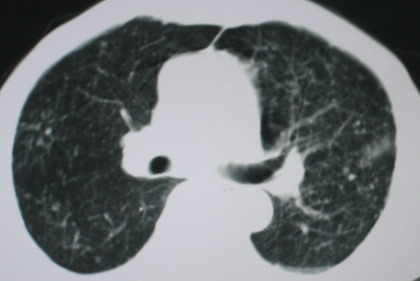

以下是引用卜一在2008-6-3 19:33:00的发言:[br]双肺结节,以双上肺分布为多,期间搀杂片状致密影及索条致密影。考虑:继发性肺结核伴血型播散可能性大。不除外肺泡ca的可能!另:椎体退变!

以下是引用panyishengct在2008-6-3 21:09:00的发言:[br]双上肺弥漫性小结节影,纵隔窗内钙化淋巴结影,考虑矽肺或/和tb可能性较大,不除外肺ca可能。腰椎考虑退变。 [br][br]